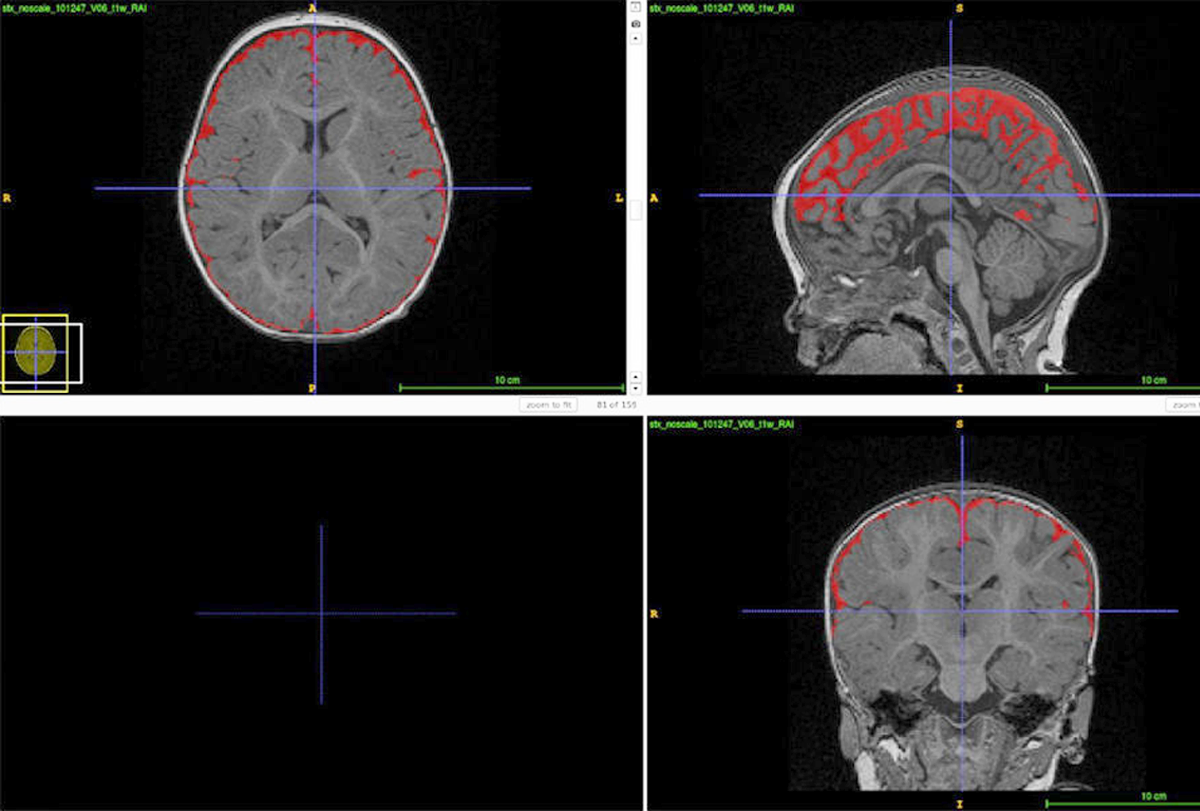

Illustration 1

Grille de quatre scanners cérébraux montrant un excès de liquide céphalo-rachidien.

En 2009, Mark Shen a remarqué quelque chose d'étrange dans le scanner cérébral d'un enfant de 6 mois dont le frère aîné était autiste : un excès de liquide entre le cerveau et le crâne. Shen - alors étudiant diplômé dans le groupe de David Amaral à l'Institut MIND de l'Université de Californie à Davis - et ses collègues ont entrepris de quantifier la quantité de liquide cérébral à partir des scanners des frères et sœurs plus jeunes d'enfants autistes. Ces "petits frères et sœurs" ont 20 fois plus de chances d'être affectés par l'autisme que la population générale.

L'équipe a rapporté en 2013 que les frères et sœurs âgés de six mois chez qui l'autisme a été diagnostiqué avaient, en moyenne, plus de liquide cérébral que les témoins. Depuis, Shen et ses collaborateurs ont confirmé le lien entre l'excès de liquide cérébral et un diagnostic ultérieur d'autisme chez des centaines de nourrissons, dont certains n'avaient pas d'antécédents familiaux d'autisme.